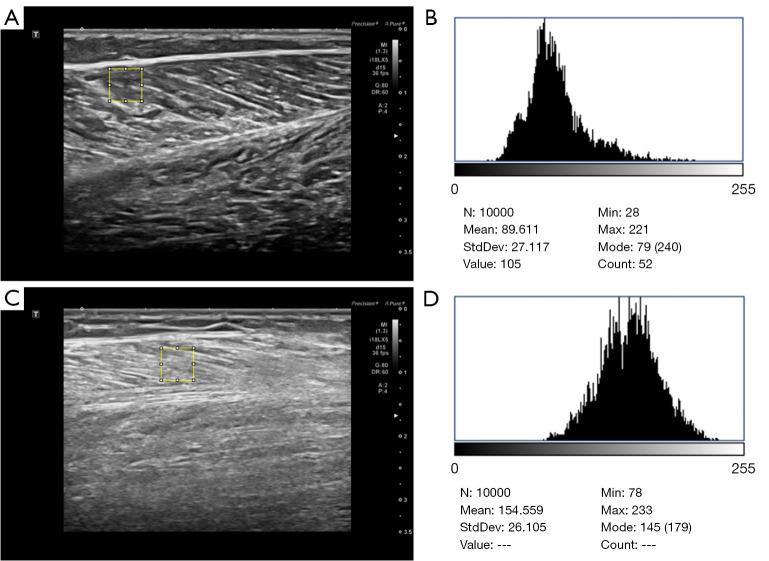

Sarcopenia, an age-related condition marked by progressive muscle loss and dysfunction, is a growing clinical and public health challenge. While current diagnostic methods involve limitations in cost, accessibility, and assessment of muscle quality, ultrasound offers a practical alternative. This study examined grayscale histogram analysis of gastrocnemius muscle ultrasound images as a novel quantitative method for diagnosing sarcopenia by evaluating its ability to detect textural changes associated with intramuscular fat infiltration and fibrosis, with the ultimate aim of establishing an accurate, accessible diagnostic approach.

A retrospective case-control study was conducted on 101 patients diagnosed with sarcopenia who were admitted to the Department of Endocrinology at Shandong Provincial Hospital between March and December 2024. Additionally, 101 healthy volunteers who underwent health examinations in our hospital during the same period were recruited as the control group. Grayscale histogram parameters, including the minimum gray value, maximum gray value, median gray value, mean gray value, standard deviation of gray values, skewness, kurtosis, and the gray values corresponding to seven percentile points (quantile 5, quantile 10, quantile 25, quantile 50, quantile 75, quantile 90, quantile 95) were extracted from the ultrasound images of the participants' gastrocnemius muscles. Statistical methods were used to analyze the differences between the sarcopenia and control groups. Receiver operating characteristic (ROC) curves were used to compare the differential diagnostic efficacy of each parameter and their combinations. Linear regression and least absolute shrinkage and selection operator (LASSO) were used to predict the probability of sarcopenia, with model performance evaluated with R values and the mean square error.

The grayscale histogram parameters of the gastrocnemius ultrasound images in the sarcopenia group, including the minimum gray value, maximum gray value, median gray value, mean gray value, standard deviation of gray values, and the gray values corresponding to seven percentile points, were significantly higher than those in the control group (P<0.001), while both the skewness and kurtosis were smaller than those in the control group (P<0.001). The gray value corresponding to quantile 75 demonstrated the best diagnostic efficacy [area under the curve (AUC) =0.988, sensitivity =96%, specificity =95%] at a cutoff of 132.5. The LASSO regression model outperformed linear regression (test set: R =0.769 0.727; mean square error =0.057 0.068).

肌肉减少症是一种与年龄相关的疾病,其特征为进行性肌肉流失和功能障碍,是一个日益严峻的临床和公共卫生挑战。虽然目前的诊断方法在成本、可及性和肌肉质量评估方面存在局限性,但超声提供了一种实用的替代方法。本研究通过评估腓肠肌超声图像的灰度直方图分析检测与肌内脂肪浸润和纤维化相关的纹理变化的能力,将其作为诊断肌肉减少症的一种新型定量方法,最终目的是建立一种准确、可及的诊断方法。

对2024年3月至12月在山东省立医院内分泌科住院的101例诊断为肌肉减少症的患者进行回顾性病例对照研究。此外,同期在我院进行健康体检的101名健康志愿者作为对照组。从参与者腓肠肌的超声图像中提取灰度直方图参数,包括最小灰度值、最大灰度值、中位数灰度值、平均灰度值、灰度值标准差、偏度、峰度以及七个百分位点(分位数5、分位数10、分位数25、分位数50、分位数75、分位数90、分位数95)对应的灰度值。采用统计方法分析肌肉减少症组与对照组之间的差异。采用受试者操作特征(ROC)曲线比较各参数及其组合的鉴别诊断效能。使用线性回归和最小绝对收缩和选择算子(LASSO)预测肌肉减少症的概率,用R值和均方误差评估模型性能。

肌肉减少症组腓肠肌超声图像的灰度直方图参数,包括最小灰度值、最大灰度值、中位数灰度值、平均灰度值、灰度值标准差以及七个百分位点对应的灰度值,均显著高于对照组(P<0.001),而偏度和峰度均小于对照组(P<0.001)。在截断值为132.5时,分位数75对应的灰度值显示出最佳诊断效能[曲线下面积(AUC)=0.988,灵敏度=96%,特异度=95%]。LASSO回归模型优于线性回归(测试集:R=0.769对0.727;均方误差=0.057对0.068)。